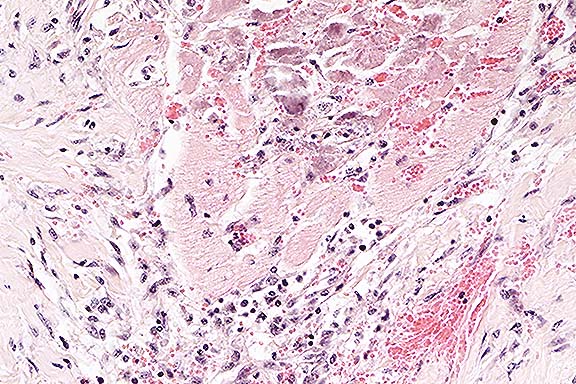

Case 23-4. Lung. Note accumulation of viable and degenerate neutrophils and squamous epithelial cells in the alveoli. 40X

Contributor's Diagnosis and Comments: Lung: Alveolitis, acute, moderate, multifocal, suppurative with intralesional keratin and meconium.

Meconium aspiration syndrome (MAS) is an important clinicopathologic condition of neonates characterized by hypoxemia, acidosis and "patchy" atelectasis. Aspiration of amniotic fluid, with or without meconium, occurs before, during parturition, or when the umbilical cord is severed (meconium in hypopharynx). The amniotic fluid serves as a vehicle to carry fetal epidermal cells, keratin and meconium into the lungs. These materials cause a foreign body reaction and chemical alveolitis. Multinucleated giant cells are sometimes seen in the lungs of animals that have aspirated several days before. Although passage of small amounts of amniotic fluid may have little clinical significance, large amounts, as observed in this foal, cause respiratory distress, atelectasis (displacement of surfactant), inflammation, and inefficient pulmonary defense mechanisms. The long-term effect of MAS in domestic animals that survive is not known. The term alveolitis was preferred to bronchopneumonia as lesions are not grossly visible (other than focal atelectasis) and the inflammatory response is centered in the alveolar region.

AFIP Diagnosis: Lung: Pneumonia, neutrophilic and histiocytic, acute, multifocal, moderate, with intralesional squamous epithelial cells, Standardbred, equine.

Conference Note: This case was studied in consultation with the Department of Prenatal, Perinatal, and Placental Pathology of the AFIP. The peripheral acinar distribution of the inflammation is unusual for aspiration. Gram stains performed at the AFIP did not demonstrate bacteria, and a Hall's bile stain did not demonstrate meconium. Thus, the cause of the pneumonia is uncertain.